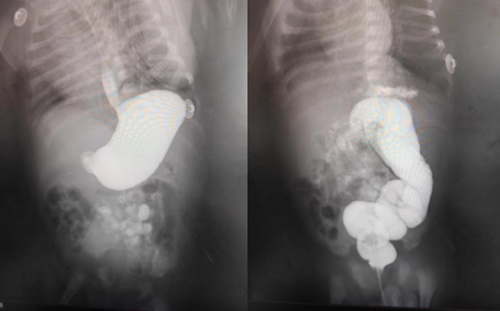

希希從剛出生3天就開始出現(xiàn)頻繁嘔吐,吃奶后就吐……希希父母趕忙帶孩子到當(dāng)?shù)蒯t(yī)院就醫(yī),雖然經(jīng)過開塞露通便、灌腸、補(bǔ)液、止吐、抗炎等治療,但一直沒有明顯好轉(zhuǎn)。焦急的爸媽帶著希希來到青島婦女兒童醫(yī)院新生兒外科就醫(yī)。經(jīng)過B超、消化道造影等檢查,接診專家判斷希?;加心c旋轉(zhuǎn)不良。

腸旋轉(zhuǎn)不良是一種先天性疾病,簡(jiǎn)單的說是胎兒的腸管先天性地沒有旋轉(zhuǎn)好,導(dǎo)致腸管分布異常。等到寶寶出生后,便會(huì)出現(xiàn)腸管不通暢、腸梗阻、嘔吐等一系列癥狀。嚴(yán)重時(shí)可發(fā)生中腸扭轉(zhuǎn),進(jìn)而發(fā)生絞窄性腸梗阻,如不及時(shí)就醫(yī)治療,往往導(dǎo)致大面積腸管缺血壞死。新生兒外科團(tuán)隊(duì)針對(duì)患兒病情實(shí)施緊急手術(shù)。術(shù)中,手術(shù)團(tuán)隊(duì)成員發(fā)現(xiàn)患兒腸管已旋轉(zhuǎn)270度!團(tuán)隊(duì)成員精準(zhǔn)操作,分離粘連、將腸管復(fù)位后,所有腸管的顏色逐漸都變得紅潤(rùn)起來。